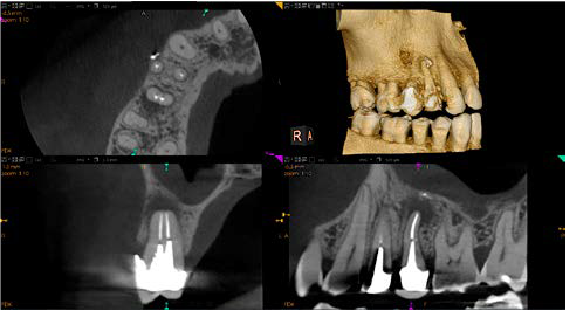

Implantes

Planifique los implantes con confianza gracias a nuestro avanzado software de planificación de implantes con coronas virtuales personalizadas y a la completa biblioteca de implantes